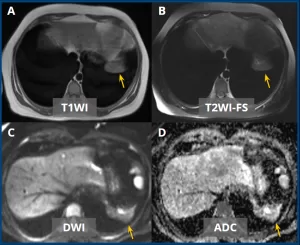

Axial MRI images in T1-weighted (A), T2-weighted with fat suppression (B), DWI (C), and ADC (D) sequences demonstrate a lesion with elongated/discoid morphology, centered at the base of the left hemithorax (yellow arrows), demonstrating isointense signal on T1, mildly hypointense signal on T2, and no diffusion restriction.